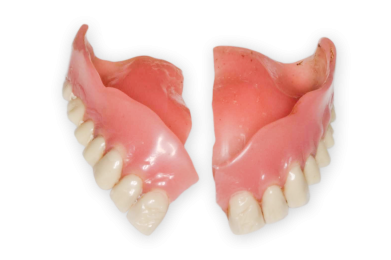

- Prothesen werden nicht mehr getragen

- Prothesen und Schleimhäute zeigen weißliche Beläge bzw. Haftcreme-Reste

- Prothesen lösen sich immer wieder unkontrolliert beim Sprechen, häufiger fallen die Prothesen einfach aus dem Mund / Sprache ist undeutlich und Person spricht auffällig wenig

- Essen wird verweigert / Teilprothesen bzw. Totalprothesen vorhanden